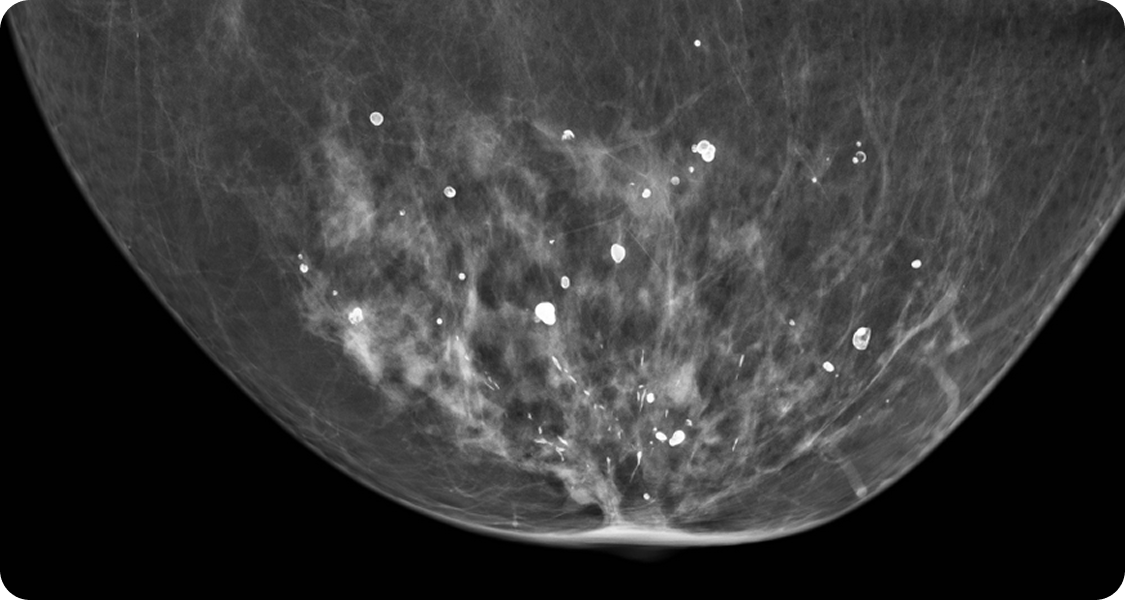

유방 내 칼슘이 쌓여 나타나는 작은 석회 알갱이로, 유방 촬영 검사(맘모그래피)에서 발견됩니다.

대부분은 양성이지만, 일부는 유방암의 초기 신호일 수 있어 정확한 진단이 필요합니다.

맘모톰 Selenia Dimensions 3D 장비는 기존 2D 촬영보다 유방조직을 세밀하게 확인할 수 있어 미세 병변 발견에 탁월합니다. 방사선량은 낮추고 정확도는 높여 조기진단에 도움을 줍니다.

연세위드유의 미세석회화 검진장비 Selenia Dimensions 3D Selenia Dimensions 3D 장비는 기존 2D 촬영보다 유방조직을 세밀하게 확인할 수 있어 미세 병변 발견에 탁월합니다.